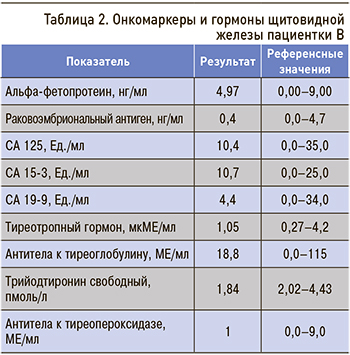

Онкомаркеры и гормоны щитовидной железы были в пределах нормы (табл. 2).